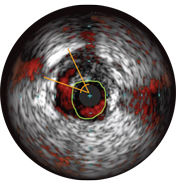

Диаметры сосудов можно определять в проксимальных и дистальных контрольных точках за счет значений диаметров просветов, средних диаметров стенок (в центральной точке между просветом и сосудом) или диаметров сосудов.

ВСУЗИ помогает более точно определить степень и тип стеноза (т.е. минимальную площадь просвета (MLA), объем бляшки и кальций). Несмотря на то что ВСУЗИ позволяет выявить разрыв бляшки, наличие тромбов и диссекции, кальций наиболее распространен при рутинных ЧКВ. Оказывая большее влияние на стратегию стентирования, кальций отображается в виде очень ярких участков с акустическим затенением, которое блокирует изображение сзади. Также могут наблюдаться реверберации.

На мальаппозицию указывает наличие крови за стратами стента. При визуализации с использованием режима ChromaFlo кровоток окрашен в красный цвет для простого выявления мальаппозиции и других особенностей просвета.